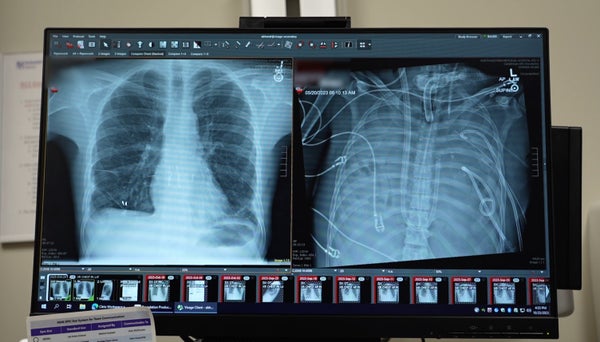

In 2023 thoracic surgeon Ankit Bharat was working at Northwestern Memorial Hospital when he was drafted to help a 33-year-old influenza patient who was on the verge of death. Bharat recalls that the man had developed a secondary infection from one of the “most dreaded bugs” in the hospital, Pseudomonas, and had been put on a ventilator. The patient’s lungs were filling with fluid and pus, his kidneys were failing, and his heart was barely working, Bharat says. “He was actively dying.”

The man needed a double-lung transplant, but there was a problem: he was too sick for Bharat and his colleagues to attempt the operation. But Bharat knew that without a working set of lungs, the patient would die regardless. He had already been on a life-support system called extracorporeal membrane oxygenation (ECMO) to oxygenate his blood, but that treatment can’t sustain a patient without lungs in their body, Bharat says.